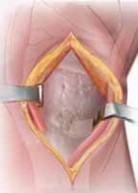

1. A routine diagnostic arthroscopy is performed.

2. The status of the lateral compartment is confirmed.

1. If unexpected lateral compartment osteoarthritis or chondral defects are found, off-loading the knee into that compartment may be detrimental to the longterm results of the surgery (

TECH FIG 1

).

3. The status of the patellofemoral compartment also is confirmed.

1. Significant patellofemoral arthritis (especially of the lateral patellar facet and lateral trochlea) can be ex-

acerbated with an HTO. Such arthritis also can be detrimental to the long-term results of the surgery.

1. Meniscal tears are débrided back to a stable base.

2. Chondroplasty or marrow stimulation is now performed. If the osteotomy is being performed together with a cartilage restorative procedure (eg, autologous chondrocyte implantation), the osteotomy is performed first and then the restorative cartilage procedures are performed, to minimize any trauma to the newly implanted pe-riosteal covering or injected cartilage cells. TECH FIG 1 • A. Arthroscopic image of the medial compartment. Note the bone exposed on the medial femoral condyle and tibia. B. Arthroscopic image following use of a microfracture technique. On entering the lateral compartment, an unexpected cartilage lesion was found on the lateral femoral condyle. Offloading the mechanical axis into the lateral compartment that already is degenerated is a

A B contraindication to the procedure.